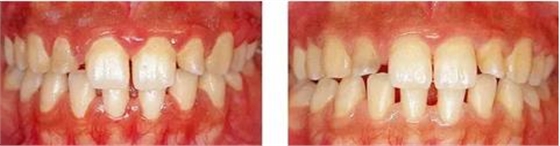

病例2 由于牙齦很脆弱,不能進(jìn)行很充分的菌斑控制,進(jìn)行了游離齦移植手術(shù)后得到改善的病例。

圖17-1(左) 刷牙時(shí)牙齦疼痛為主訴的17歲女性患者的初診正面照片。牙齦炎癥嚴(yán)重,下頜前牙區(qū)黏膜能看到很多血管。

圖17-2(右) 初期治療結(jié)束后的正面照片。牙齦炎癥減輕了,但牙齦還是非常脆弱,所以菌斑難以控制。